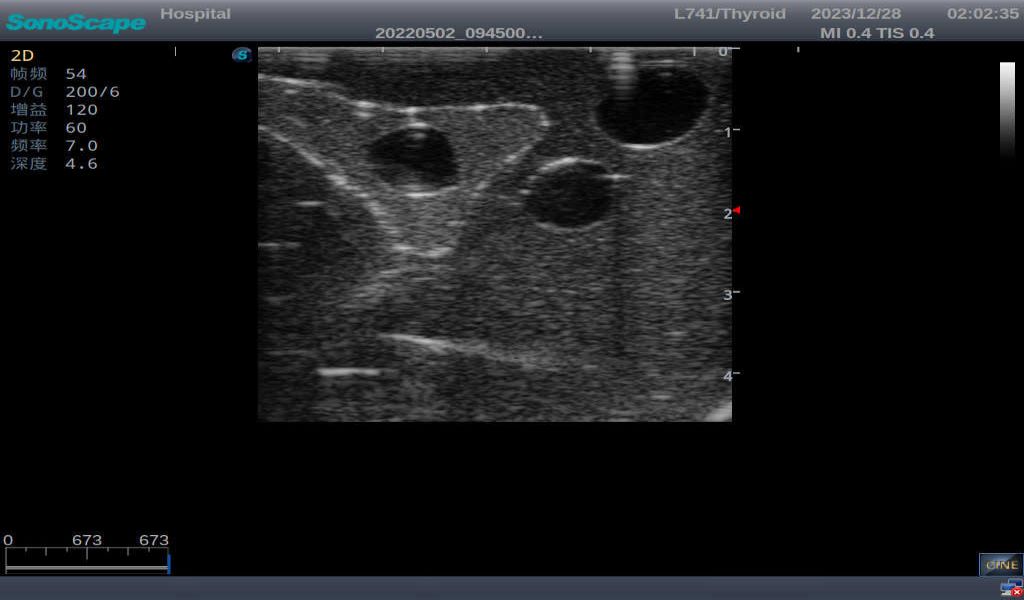

3)       It comes with four (4) thyroid modules and can show five (5) ultrasonic images: normal thyroid, thyroid adenoma, thyroid cancer, nodular goiter, thyroid cyst

Normal thyroid with homogeneous parenchymal echo and well-defined capsule

Thyroid adenoma with well-defined border and smooth uniform halo

Nodular goiter with irregular border and varying sizes of low echo, isoechoic, or high echo nodules

Thyroid cyst, which fluid area, dark and echo-free area can be seen